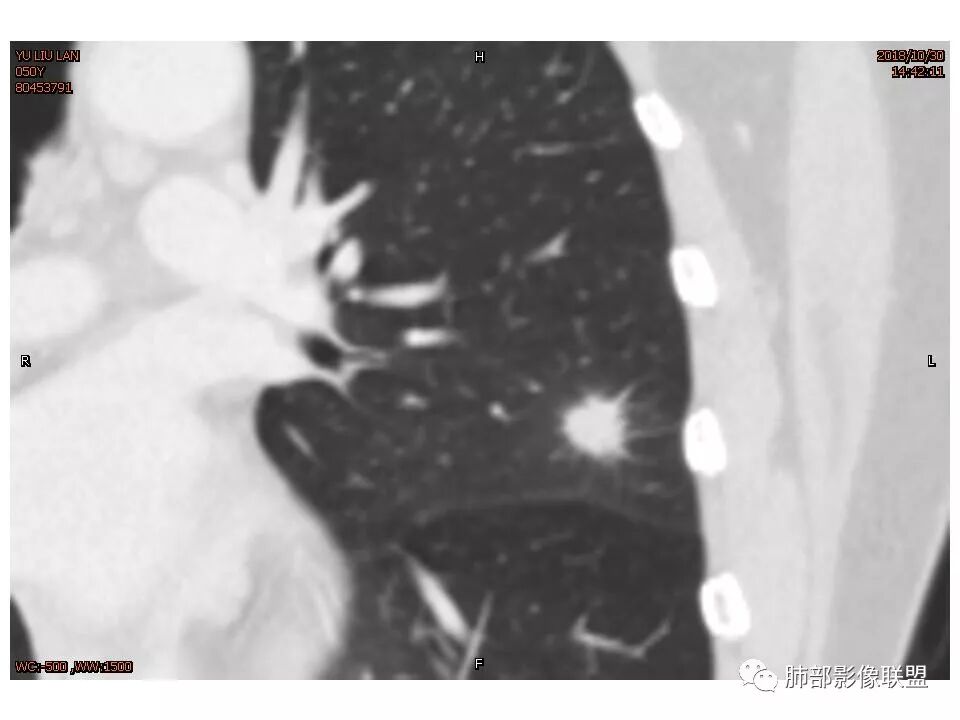

女,50。实性不规则结节,大小12*13mm,分叶、毛刺、胸膜凹陷,牵拉力强,增强渐进性强化,动脉期强化20,静脉期还有进一步强化。边缘强化,点状坏死。

其内血管被破坏。

左肺上叶结节,部分边缘膨隆,边缘毛刺,斜裂牵拉,增强中度强化,血管穿行,血管略增粗。考虑肺癌,腺癌可能性大,鉴别肉芽肿性炎

左肺上叶结节影,病灶周围呈磨玻璃样改变边缘见毛刺、分叶及胸膜牵拉,增强扫描病灶明显强化,病灶未跨叶间裂,考虑炎性病变,待除外小腺癌。

左肺上叶结节,边缘毛糙,有毛刺分叶胸膜牵拉,邻近血管稍增粗,似有月牙铲,但增强感觉坏死有点多,可疑鬼脸,常规需排除腺癌,建议结合夹馍抗原除外隐球菌,治疗后复查。

结节样病灶,u型征,病灶内可见细支气管管,增强可见血管进入,略增粗,病灶周围有晕,有软毛刺,局部叶间胸膜有牵拉,考虑良性炎性病灶,抗炎后复查。

尽管有收缩性改变,但是部分层面可见病灶有膨胀性表现,增强后病灶内可见血管影,局部血管凹凸不平,再加上病灶的分叶,胸膜凹陷征象等等,是不能排除恶性病变,写报告时,仍然需要把恶性病变靠前,腺癌第一考虑,其次炎性肌纤维母,再次再考虑炎性病变。

血管贴边,但没有明显压迫征象。明显强化。局部膨隆,毛刺,分叶。

胸膜牵拉,这些都支持恶性

恶性征像,胸膜牵拉,浅分叶,毛刺,增强强化明显,净增超25hu。血管边缘模糊串珠样改变。

细小毛刺,梳状平行,周围边缘模糊晕,血管未收侵犯,支气管未见牵拉扩张,多条淋巴道与胸膜相联,倾向于炎性病变

1.胸膜下略不规则实性密度结节影,孤立,缺乏典型深分叶,可见淡薄边界模糊磨玻璃晕,可见相对细长软毛刺。

2.如南边老师分析,病灶缺乏边缘膨隆优势,甚至部分平直内收。

3.病灶收缩力不强,整体强化程度不显著。

4.综上,病灶更符合炎性,如隐球菌感染等,而不大符合肺腺癌。具体到机化性肺炎略有些出乎预料。